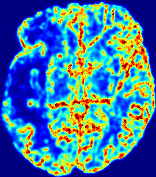

LesionRefer to captionRefer to captionRefer to captionRefer to captionRefer to captionRefer to caption𝐕rgbsubscript𝐕𝑟𝑔𝑏{\bf{V}}_{rgb}Refer to captionRefer to captionRefer to captionRefer to captionRefer to captionRefer to caption𝐕2subscriptnorm𝐕2{\|\bf{V}}\|_{2}Refer to captionRefer to captionRefer to captionRefer to captionRefer to captionRefer to captionRefer to caption3.53.53.52.82.82.82.12.12.11.41.41.40.70.70.70.00.00.0(mm/s)𝑚𝑚𝑠(mm/s)D𝐷DRefer to captionRefer to captionRefer to captionRefer to captionRefer to captionRefer to captionRefer to caption0.0200.0200.0200.0160.0160.0160.0120.0120.0120.0080.0080.0080.0040.0040.0040.0000.0000.000(mm2/s)𝑚superscript𝑚2𝑠(mm^{2}/s)Slice #1Slice #2Slice #3Slice #4Slice #5Slice #6

Figure 4: PIANO feature maps for another patient in the ISLES 2017 training set, where the lesion is located in the right hemisphere. Top row: segmented stroke lesion region (white) on different slices. The corresponding slices for the PIANO feature maps are shown in the following rows.

For a better insight into an estimated velocity field 𝐕𝐕{\bf{V}} and diffusion field 𝐃𝐃{\bf{D}}, we compute the following maps: (1) 𝐕rgbsubscript𝐕𝑟𝑔𝑏{\bf{V}}_{rgb}: Color-coded orientation map of 𝐕=(Vx,Vy,Vz)T𝐕superscriptsuperscript𝑉𝑥superscript𝑉𝑦superscript𝑉𝑧𝑇{\bf{V}}=(V^{x},V^{y},V^{z})^{T}, obtained by normalizing 𝐕𝐕{\bf{V}} to unit length and mapping its 3 components to red, green, blue respectively; (2) 𝐕2subscriptnorm𝐕2\|{\bf{V}}\|_{2}: 222 norm of 𝐕𝐕{\bf{V}}; (3) D𝐷D: scalar field in Eq. 5.

Fig. 3 and Fig. 4 show the PIANO feature maps estimated from two ISLES 2017 patients: all are highly consistent with the lesion in both cases. Details of the blood flow trajectories are revealed in 𝐕rgbsubscript𝐕𝑟𝑔𝑏{\bf{V}}_{rgb} by the ridged patterns and the sharp changes of colors in the unaffected (right) hemisphere, while the flat patterns appearing within the lesion provide little directional information about the velocity and indicate low velocity magnitudes. Velocity magnitudes are more directly visualized via 𝐕2subscriptnorm𝐕2\|{\bf{V}}\|_{2}, from which one can easily locate the lesion where 𝐕2subscriptnorm𝐕2\|{\bf{V}}\|_{2} is low. D𝐷D also indicates lower diffusion values in the lesion, though with less contrast potentially due to the fact that it captures the accumulated effect of CA diffusion at the voxel-level.